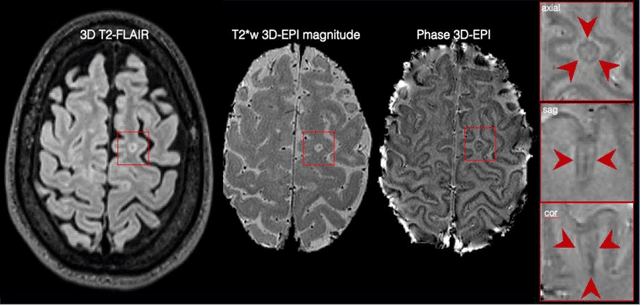

Abstract:The current multiple sclerosis (MS) diagnostic criteria lack specificity, and this may lead to misdiagnosis, which remains an issue in present-day clinical practice. In addition, conventional biomarkers only moderately correlate with MS disease progression. Recently, advanced MS lesional imaging biomarkers such as cortical lesions (CL), the central vein sign (CVS), and paramagnetic rim lesions (PRL), visible in specialized magnetic resonance imaging (MRI) sequences, have shown higher specificity in differential diagnosis. Moreover, studies have shown that CL and PRL are potential prognostic biomarkers, the former correlating with cognitive impairments and the latter with early disability progression. As machine learning-based methods have achieved extraordinary performance in the assessment of conventional imaging biomarkers, such as white matter lesion segmentation, several automated or semi-automated methods have been proposed for CL, CVS, and PRL as well. In the present review, we first introduce these advanced MS imaging biomarkers and their imaging methods. Subsequently, we describe the corresponding machine learning-based methods that were used to tackle these clinical questions, putting them into context with respect to the challenges they are still facing, including non-standardized MRI protocols, limited datasets, and moderate inter-rater variability. We conclude by presenting the current limitations that prevent their broader deployment and suggesting future research directions.